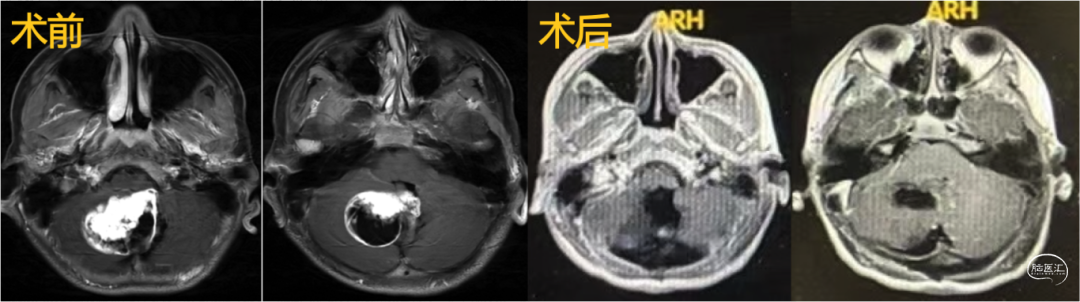

2.小脑-脑干肿瘤切除术